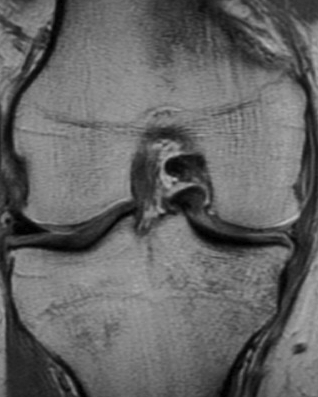

Signs of bucket handle tear meniscus

1. Double PCL sign

- medial Meniscus

2. Absent bow tie sign

- should see bow tie image on 2 consecutive sagittal slices of 5 mm

3. Fragment in notch sign

4. Anterior flipped meniscal sign

- torn fragment flips over the anterior horn of the affected meniscus

5. Truncated meniscus